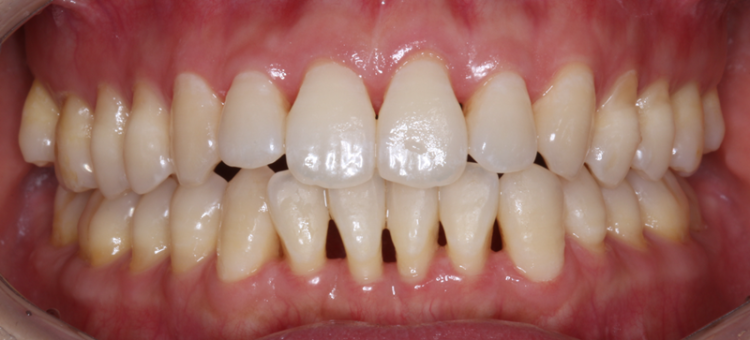

많은 환자분들이 치주 질환으로 내원하시면서 말씀하시는 내용 중 하나가 치아가 점점 길어지고 치아 사이에 구멍이 뻥 뚫린 것처럼 치아 사이에 검은 점이 생겼다 말씀을 주십니다.

3232235521_OeVnuySU_661d352c64cb0c28e93fadcc058768548ad62d7c.png 하지만 치아가 영양을 섭취해서 길이가 자랄 일은 없고 갑자기 하루아침에 구멍이 생기는 일은 없습니다.

우리의 잇몸 속은 치아가 빠지지 않게 단단히 지탱해 주는 치조골과 신경, 치아 뿌리가 자리하고 있는데요.

3232235521_I87ypub6_9a07de343401756a31a98c851f149eb5ea605f14.png만약 이 잇몸뼈가 녹게 된다면 잇몸이 내려앉아 앞서 말씀드렸던 것처럼 치아가 길어진 것 같고 구멍이 난 것처럼 느껴지실 수 있습니다.

그렇다면 이 치조골은 왜 녹아서 잇몸 내려앉음 현상이 나타나게 되는 걸까요?